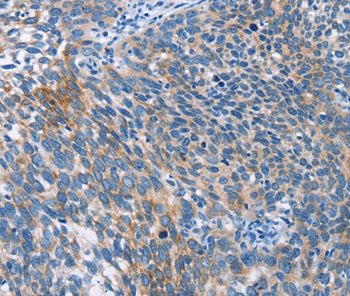

Immunohistochemical analysis of paraffin-embedded Human thyroid cancer tissue using #37415 at dilution 1/50.

Immunohistochemical analysis of paraffin-embedded Human cervical cancer tissue using #37415 at dilution 1/50.